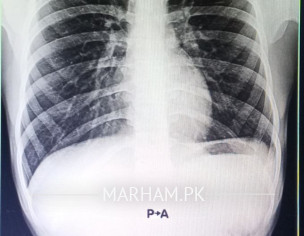

Could the obliteration of the left costophrenic angle on my chest X-ray indicate a pleural effusion or another condition?

It’s normal Xray

Do you have any symptoms or previous history of respiratory problems. This could be due to technical quality of Xray. But ultrasound of chest can give you better answer.

On CXR PA view more than 200ml will obsure costophrenic angle..Seems Normal

Normal xray